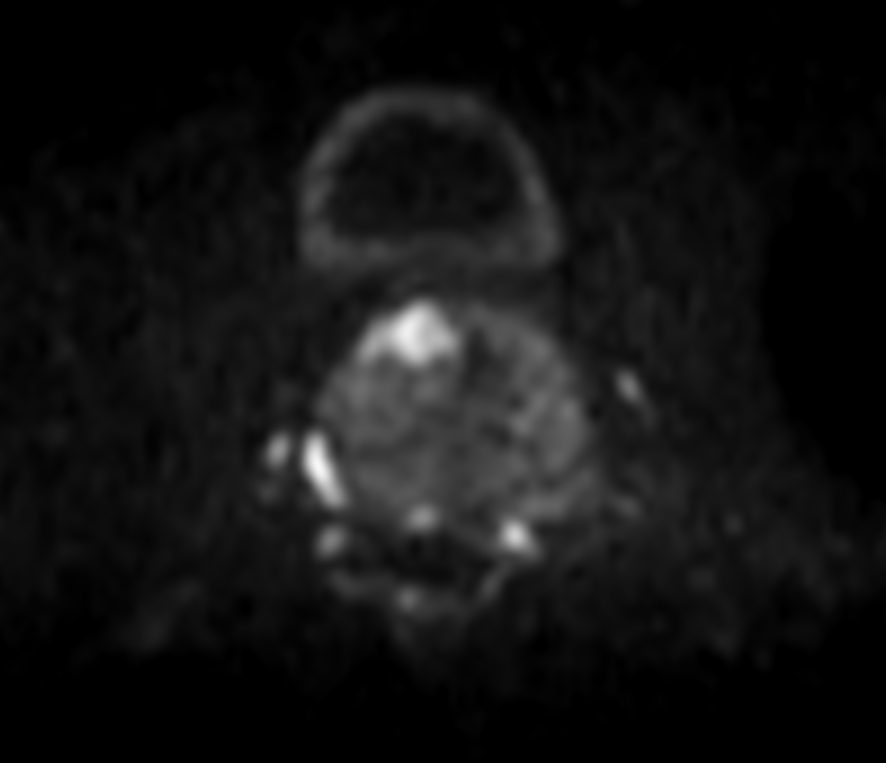

Axial DWI (b800)